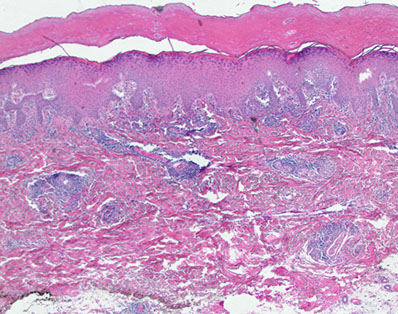

"Fingers" that point down are rete ridges, with papillary dermis (pink hyaline) right next to it, and a dermal papilla interlocking with the rete ridges (with  little capillaries in them)

- blood vessels in dermal papilla takes away wast products from the epidermis

- all epidermal layers throughout the body do not have vessels within them, but have vessels in the stroma to nourish them with oxygen and provide layer to grow on

Pink bundles of spindle cells, can be:

1) Dense regular connective tissue, dense collagen

2) Nerve

3) Smooth muscle

Dermis

Irregular dense connective tissue

- papillary dermis is fine, thin light pink collagen bwt the rete ridge and dermal papilla (c BV)

- reticular dermis if fatter, darker strands of collagen deeper down

Superficial vascular plexus - slightly larger layer of BVs that separates the papillary and reticular dermis

Arrow to pink papillary dermis, to the left is a rete ridge, to the right, an interlocking dermal papilla